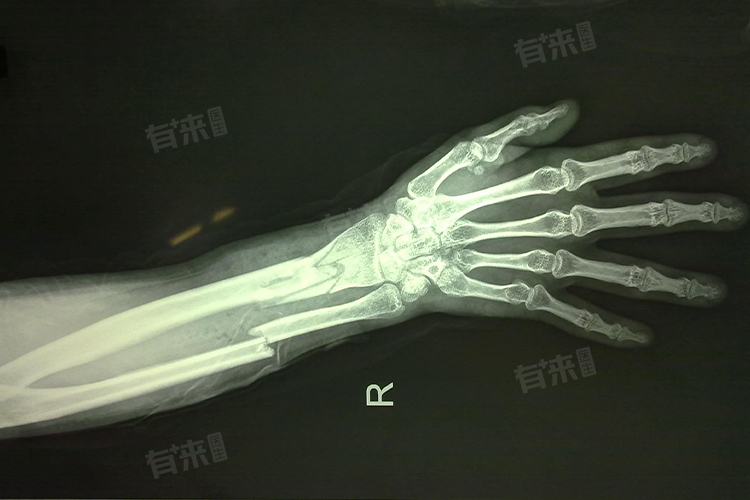

3、X线平片检查

X线平片是骨折诊断的常规手段,也是判断骨折是否移位的重要依据。通过X线平片,医生可以清晰地观察骨折线的位置、形态以及骨折断端的对位情况,从而准确判断骨折是否移位。